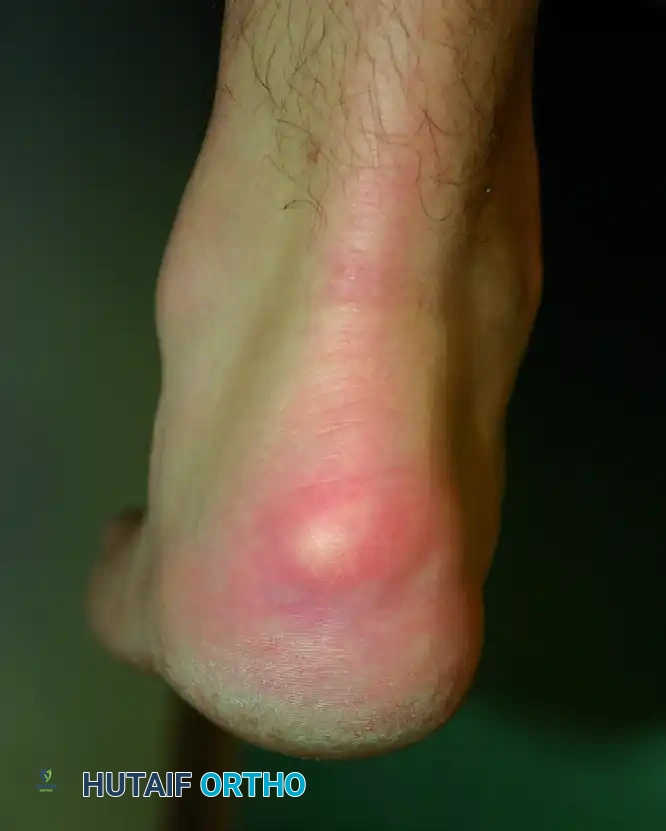

Insertional Achilles tendinitis is a complex triad of pathologies occurring at the tendon-bone interface:

1. Haglund Deformity ("Pump Bump"): A prominent exostosis on the posterosuperior aspect of the calcaneal tuberosity.

2. Retrocalcaneal Bursitis: Inflammation of the bursa that normally acts as a lubricating cushion between the anterior aspect of the Achilles tendon and the posterosuperior calcaneus.

3. Insertional Tendinosis: Intratendinous degenerative tearing, often accompanied by dystrophic calcification or frank ossification within the distal tendon fibers.

Patients rarely report an acute traumatic event. The classic presentation is a slow, insidious onset of pain and swelling directly at the tendon insertion.

* Symptoms: Progressive inability to wear closed-back shoes due to direct mechanical pressure. Patients frequently report severe "start-up" pain after periods of rest, particularly when taking their first steps in the morning.

* Physical Examination: Direct palpation elicits exquisite tenderness over the retrocalcaneal bursa (anterior to the tendon) or centrally over the tendon insertion. A visible and palpable bony prominence is usually present. In advanced cases, the tendon itself becomes boggy, thickened, and nodular.